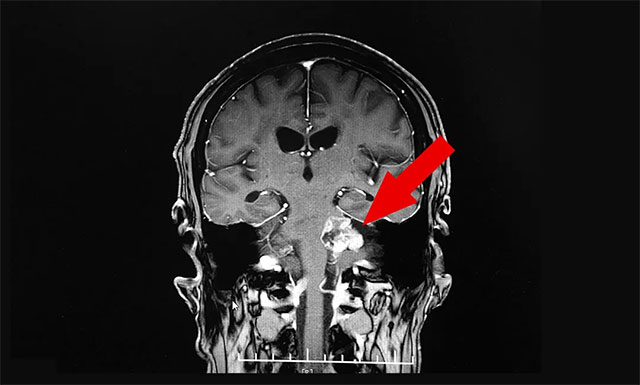

“因为老伴肢体功能恢复还不错,我们打算让他回家休养,而三个多月前老伴在外院和来蓝十字时做的都是头部CT检查,检查结果除了脑梗病症未见明确其他异常。为了让老伴放心出院,进一步了解其脑部情况,在周主任的建议下他进行了头部MRI检查,在查看影像结果时,细心的周主任却意外发现老伴左侧桥小脑角区有病灶,大小约为2.5cm×3.3cm,同时周主任还告诉我们,从影像资料上看老伴左侧听神经干增粗,很可能是听神经瘤”,听到此,管女士如五雷轰顶般顿时懵了。

随后,周主任仔细询问了患者的听力情况,据王先生反映,其听力近两年确实有所下降,但想着可能是自己年龄大的缘故,就没太在意。经过周主任细心检查,患者两侧听力都有所下降,但其左侧听力下降得更为严重。

▲ 细心的周主任发现了患者的新病症——“听神经瘤”

“周主任很专业又认真负责”,管女士对此说道:“为了能确诊,周主任还特邀医院神经外科6A病区主任侯增欣进行会诊,根据老伴的头部核磁共振检查结果,并结合他已出现的症状,最终老伴确诊为听神经瘤。而对于治疗,周主任和侯主任一致认为,由于老伴年龄较大,又身患多种疾病,如果手术,风险会比较大,建议我们放射治疗。”

当听到周君主任说听神经瘤是颅内一种良性肿瘤,可以治疗时,管女士和儿子才终于松了一口气,对于他们来讲,老伴遭受的已经很多了,真不愿意他再遭受任何疾病的折磨了。